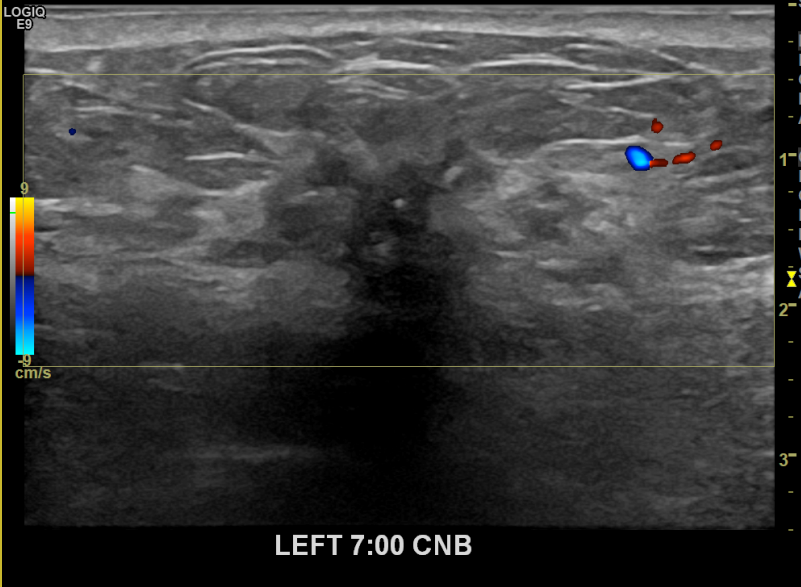

상기환자 좌측 유방통있어 내원하신 60대여성분으로 좌측 유방멍울 조직검사 시행후

유방암진단되셨습니다.